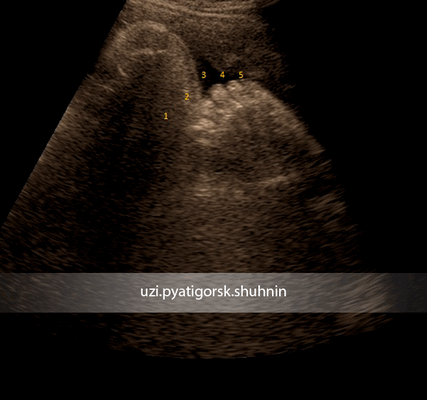

Стопа плода в норме

Постаксиальная полидактилия, визуализирован дополнительный 6-ой палец стопы плода